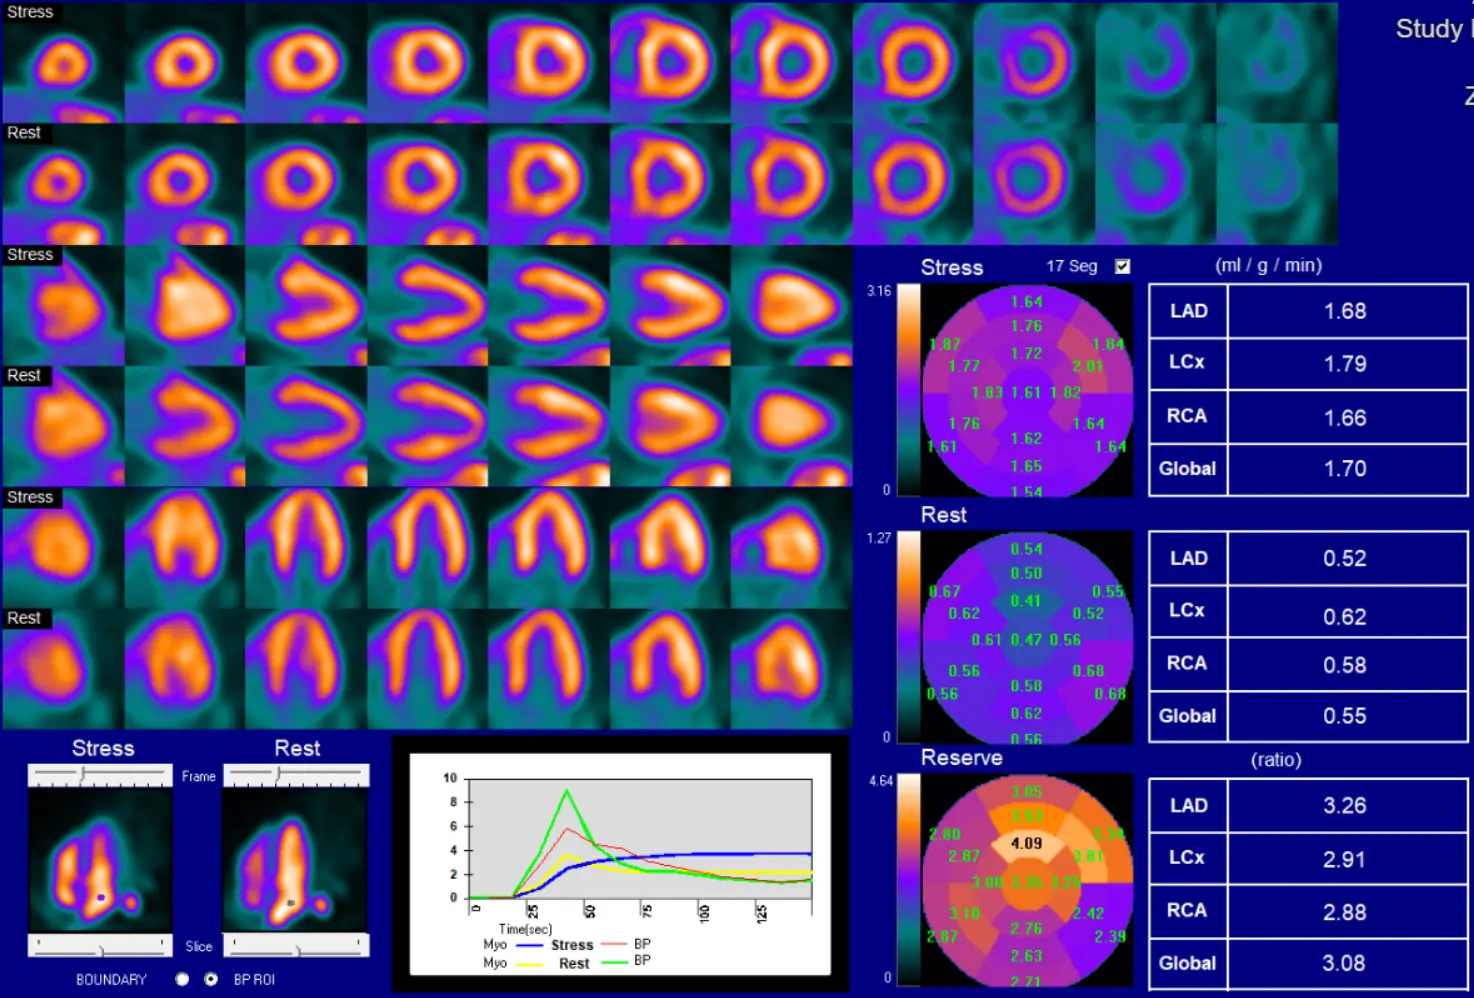

Reporting Flows

- Post-CABG you divide circulation between native and graft circulation. In the native circulation, physiology rapidly deteriorates (→ low flow). So we will typically see greater amounts of calcification in native circulation and low flow. This is not a reflection of graft closure, rather it is progression of native disease post-CABG.

- ⚠️ Be careful about reporting flows post-CABG so that referring doctor is not concerned about low flows and inadvertently sending patient to cath lab. If normal, Bateman will report them. If not normal (especially globally), it is probably best to not report them.

- ‘Not reported because not clinically relevant.’

- Other conditions where reporting flows may not be clinically relevant would be liver failure, renal failure.

- At , tracer has has not entered the heart

- At the peak it has entered the heart

- At the plateau, it has now entered the myocardium

- Initially, counts higher in blood pool than myocardium → then flips

- So at the peak, the green curve will be highest

- In the plateau phase, the signal-to-noise reflects the counts in myocardium (blue) and blood pool (red)

- Resting flows can be documented as high if the graph starts at is above 0.

- Generally peak rest blood pool (green) is 30% higher than peak stress blood pool (red).

- If < 30%, then potentially problematic for flow calculation

- You should expect a sharp rise and fall for the blood pool curves before the plateau phase. If it is wide, then there may be a technical issue.

- Compartment models are more sensitive if the QC is problematic.

Below is an example of impaired quality due to a technical issue, such as poor IV affecting infusion, long IV tubing, etc.